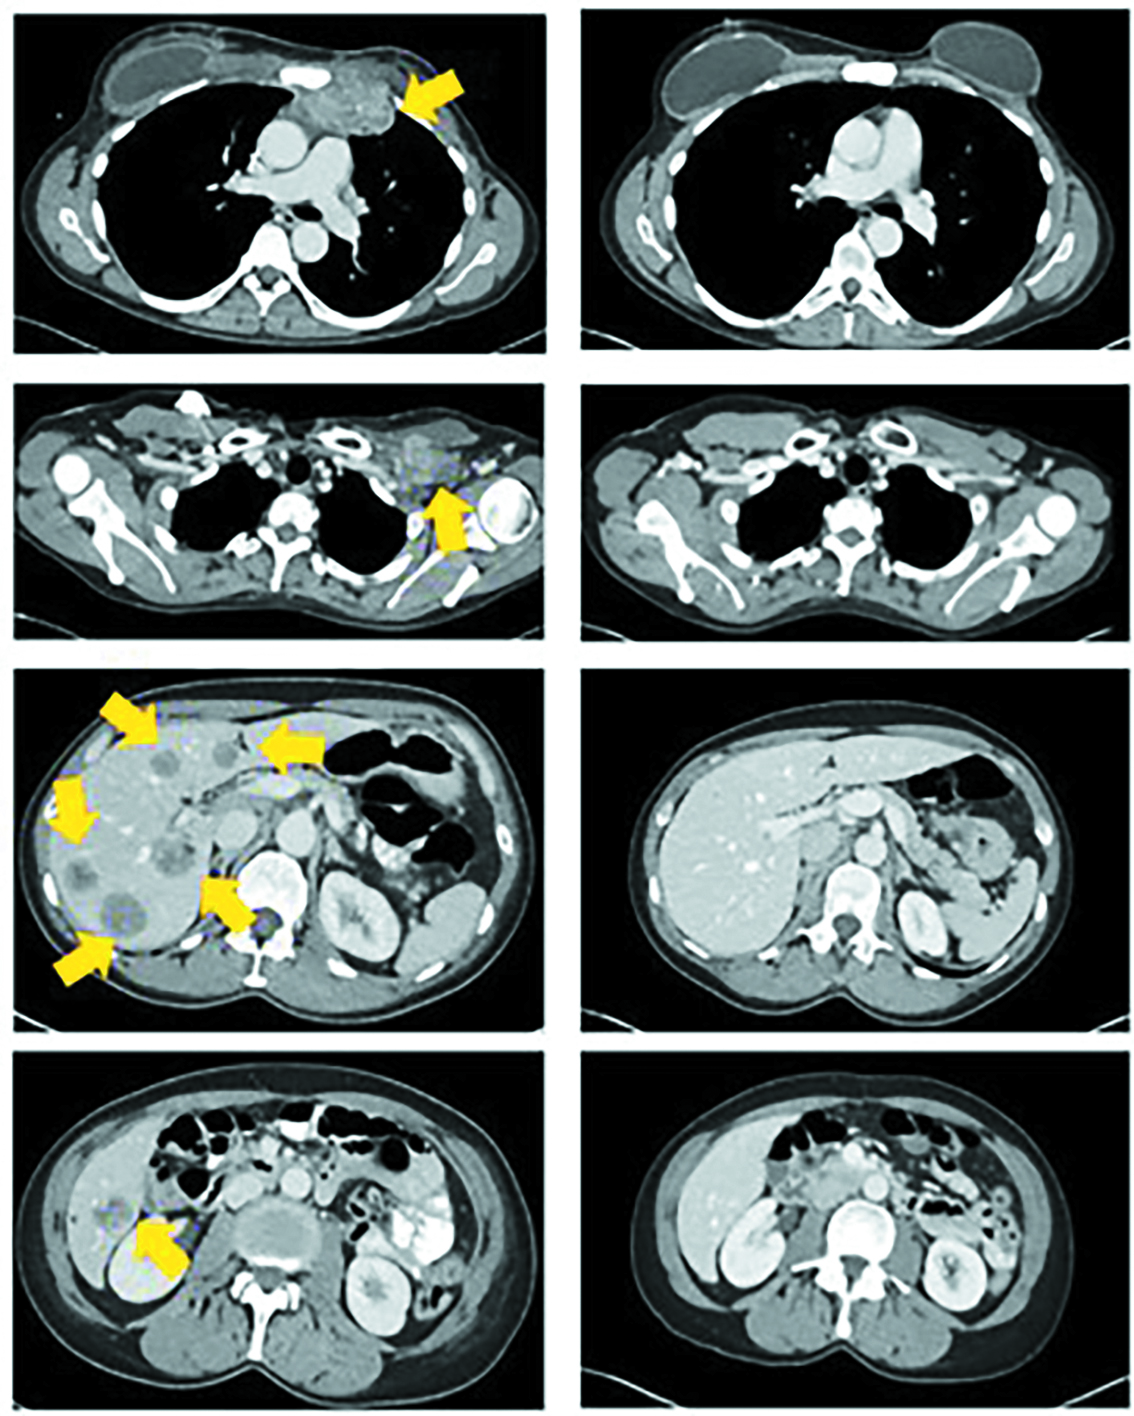

С внедрением новых методов секвенирования ДНК и РНК, с созданием баз данных появились возможности выявления неоэпитонов и создания технологий «обучения» нормальных Т-клетки способности атаковать и уничтожать опухолевые клетки (рис. 11).

Рис. 11. Компьютерная томография за неделю до инъекции лимфоцитов (слева) и через 22 месяца после нее (справа); стрелками показаны деградировавшие опухоли / Fig. 11. Computed tomography one week before the injection of lymphocytes (left) and 22 months after it (right); arrows indicate degraded tumors